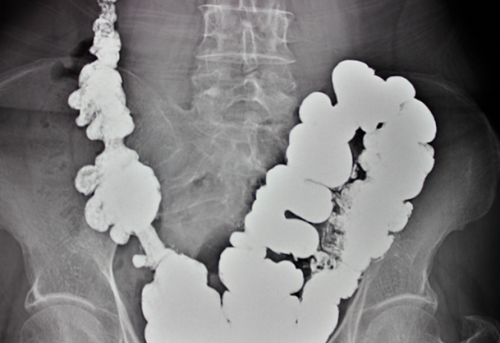

осложнения является колоноскопия. При данной процедуре

лечебный характер. При данном методе

диагностическая процедура, но и носить

Колоноскопия: